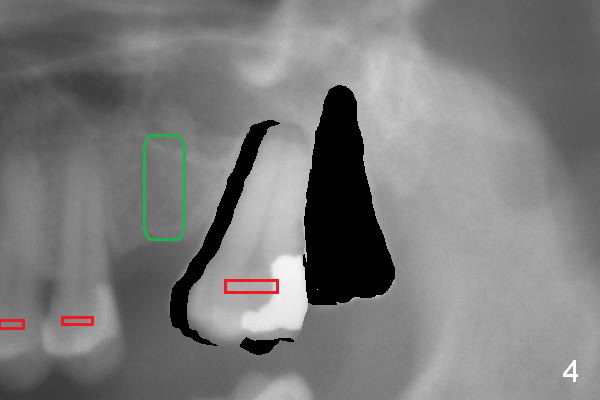

When the tooth #15 is distalized (Fig.3), place an implant at #14 (Fig.4 green), parallel to the tooth #13 and extract #16 (black). When the implant osteointegrates, place an abutment (Fig.5 pink), provisional (white) and bracket at #14. The implant is used as an anchorage to further distalize #15 until the latter reaches the normal position (Fig.6). CT study shows how much the tooth movement is needed prior to implantation.